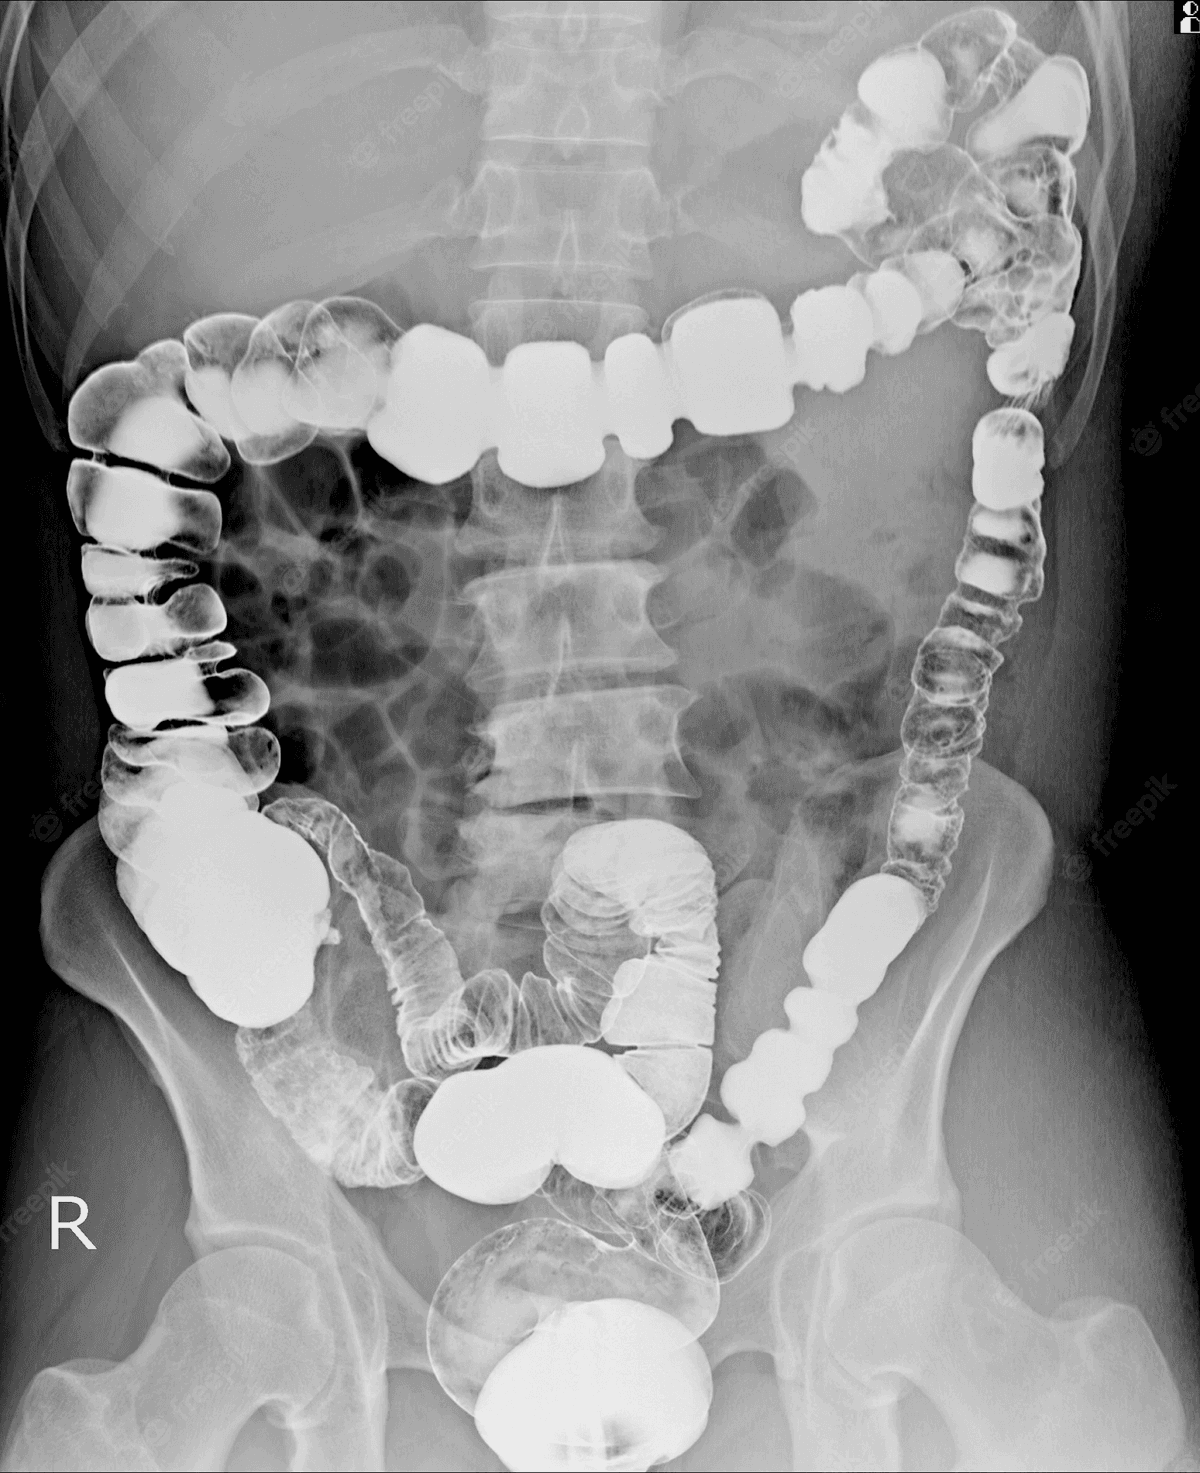

Dấu hiệu viêm đại tràng thường gặp mà bạn cần biết

Viêm đại tràng là bệnh lý tiêu hóa có nhiều biểu hiện phức tạp, gây phiền toái đến sinh hoạt và công việc – học tập. Dấu hiệu viêm đại tràng rất đa dạng, thông thường người bệnh sẽ có cảm giác đau tức bụng, đại tiện bất thường, mệt mỏi, sụt cân nhanh. Hãy […]

Đau đại tràng: Biểu hiện và cách chữa trị

Đại tràng bị viêm thường dẫn đến triệu chứng đau kéo dài, cơ thể kém hấp thu khiến người bệnh dễ suy kiệt. Hiểu về chứng đau đại tràng cũng như mức độ nguy hiểm của tình trạng này sẽ giúp người bệnh chủ động trong việc thăm khám và chữa trị, đảm bảo chất […]

Viêm đại tràng có nguy hiểm không? Cách điều trị

Viêm đại tràng là bệnh lý phổ biến tại đường tiêu hóa và là bệnh có nguy cơ tiến triển thành ung thư khá cao. Vì vậy, việc nắm rõ viêm đại tràng có nguy hiểm không và những thông tin liên quan đến căn bệnh này là vô cùng cần thiết. Từ đó, người […]

Các bệnh về đại tràng phổ biến và nguyên tắc điều trị

Đại tràng là cơ quan tiêu hóa rất quan trọng, tham gia vào quá trình hấp thụ dinh dưỡng và đào thải các chất. Cơ quan này có thể không thực hiện tốt các chức năng kể trên nếu gặp phải các bệnh lý. Hãy tìm hiểu các bệnh về đại tràng phổ biến và […]